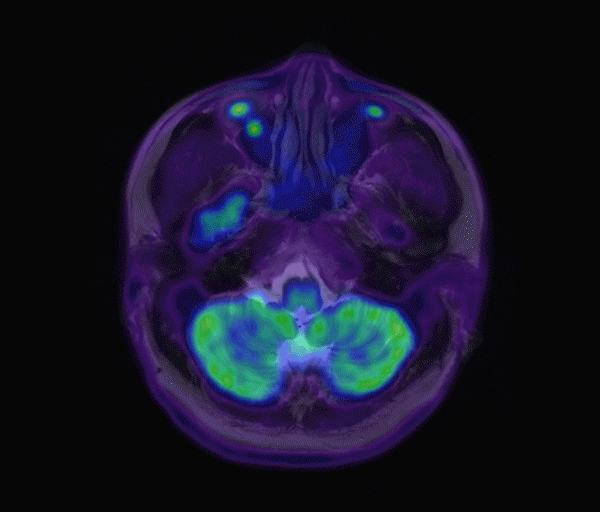

基于這種現(xiàn)狀,深圳先進(jìn)院、中大腫瘤與聯(lián)影醫(yī)療三方聯(lián)合,提出了一種“基于生成對(duì)抗網(wǎng)絡(luò)的多任務(wù)深度學(xué)習(xí)模型”,可以單從原始未經(jīng)衰減校正的PET圖像(NAC PET)中去除噪聲和偽影,生成衰減校正 PET圖像(sAC PET)以及相對(duì)應(yīng)的MR解剖定位圖像(sMR)。

通過該模型生成的sAC PET和sMR圖像與真實(shí)AC PET和真實(shí)MR圖像對(duì)比,兩組圖像具有較高相似性。

這意味著患者只需要做單一的PET檢查,就能同時(shí)獲得生理和結(jié)構(gòu)成像。